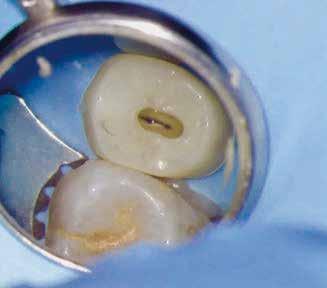

1. a–g. ábrák: A direkt pulpasapkázás lépései. Kiindulási bitewing-felvétel: A meglévő restaurátum közel helyezkedett el a pulpakamrához (a). Kiindulási periapicalis felvétel: Nincs periapicalis elváltozás fennállására utaló jel (b). A pulpaexpozíció (c). A vérzéscsillapítás céljából 20 másodpercen keresztül steril vattagombóccal történő kompressziót követően látható pulpaseb (d). A pulpasapkázás céljából behelyezett anyag, a széli részek tisztázása előtt készült felvétel (e). A röntgenárnyékot nem adó ideiglenes tömés behelyezése után készült felvétel (f). Az első ülés végén a röntgenárnyékot nem adó ideiglenes töméssel ellátott fogról készített röntgenfelvétel (g).

2. ábra: A hat hónapos kontroll alkalmával készített röntgenfelvételen vastag dentinhíd látható a pulpasapkázó anyag alatt.

3. ábra: A hároméves kontroll alkalmával készített röntgenfelvételen megfigyelhető a restaurátum pontos illeszkedése.

A diagnózisunk reverzibilis pulpitis volt. Periapicalis elváltozás jelenlétét nem vélelmeztük. A fogban lévő amalgámtömés eltávolítása során körülbelül egy 3 mm átmérőjű pulpaseb keletkezett a buccalis pulpaszarvnak megfelelően (1. a–g. ábrák) Mivel nem tapasztaltunk jelentős vérzést, és a diagnózisunk reverzibils pulpitis volt, ezért a direkt pulpasapkázás elvégzése mellett döntöttünk.

A kezelést követően a beteg tünetmentes volt. A kérdéses fog a kontrollvizsgálatok során végzett szenzibilitástesztekre fiziológiás reakciókat adott. A hat hónapos kontroll alkalmával készített röntgenfelvételen a sérülésnek megfelelően széles dentinhidat észleltünk (2. ábra). A restaurátum a hároméves kontroll során is megfelelőnek bizonyult (3. ábra)